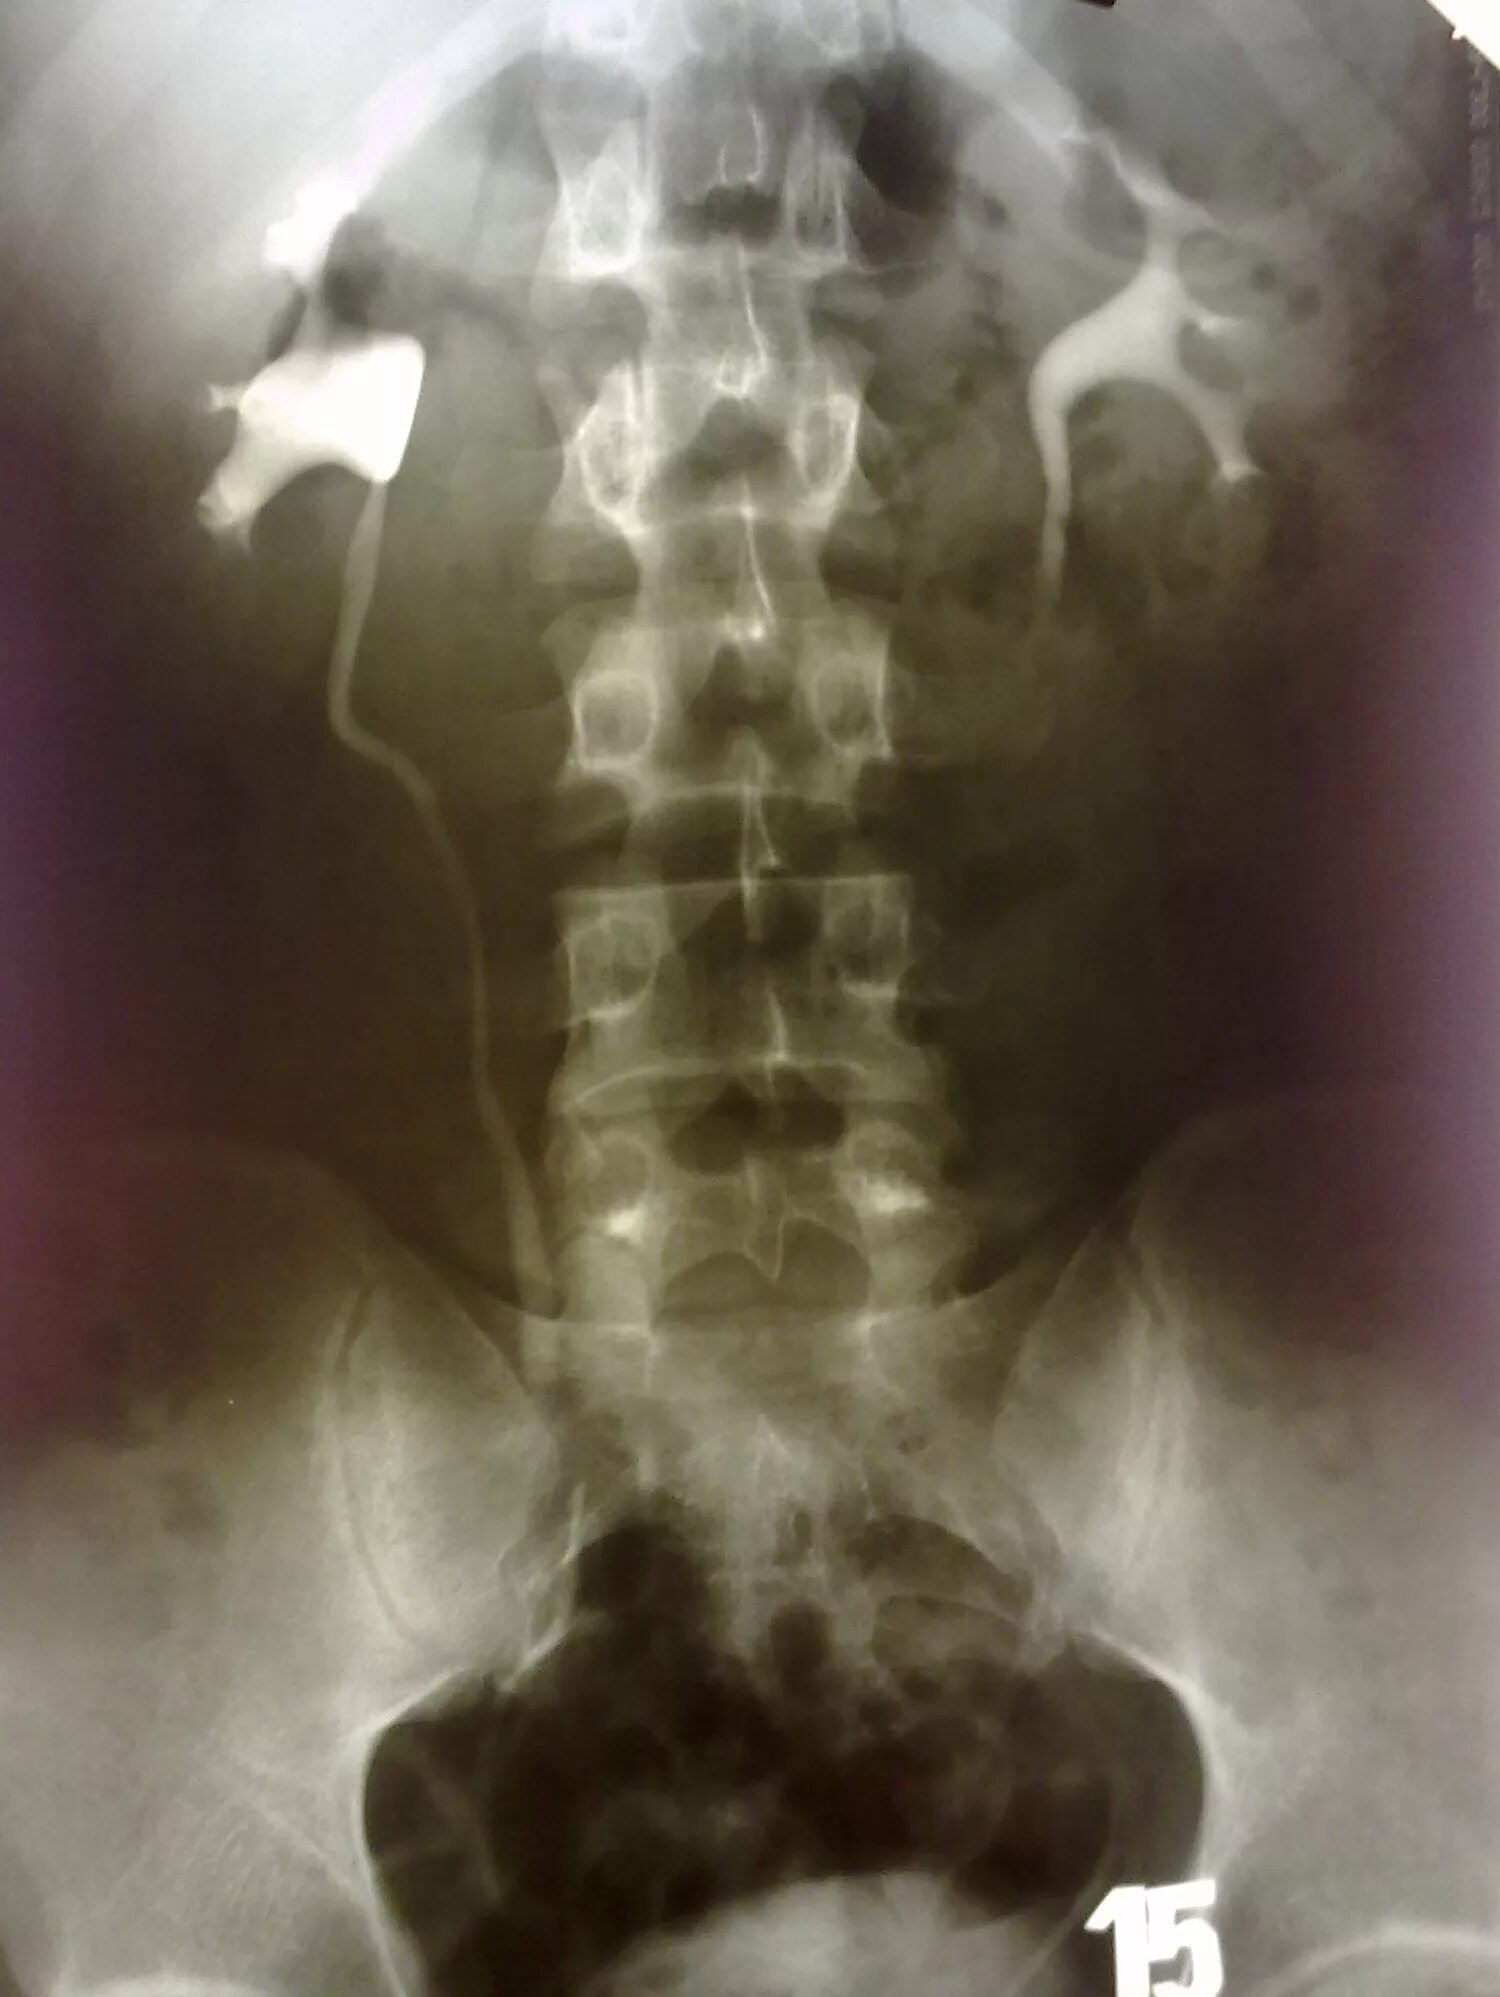

Псоас симптом